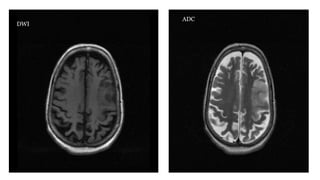

DWI and ADC(diffusion-weighted imaging and apparent diffusion coefficient) • These "blocky" images show how easily water moves around • Restricted diffusion occurs in stroke, abscesses and cellular tumors

DWI and ADC •is a commonly performed MRI sequence for evaluation of acute ischemic stroke, and is sensitive in the detection of small and early infarcts. Conventional MRI sequences (T1WI, T2WI) may not demonstrate an infarct for 6 hours, and small infarcts may be hard to appreciate on CT for days, especially without the benefit of prior imaging. • Increased DWI signal in ischemic brain tissue is observed within a few minutes after arterial occlusion and progresses through a stereotypic sequence of apparent diffusion coefficient (ADC) reduction, followed by subsequent increase, pseudo-normalization and, finally, permanent elevation. Reported sensitivity ranges from 88-100% and specificity ranges from 86-100%.